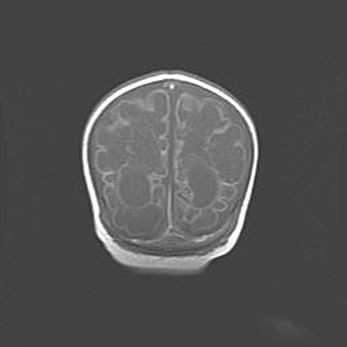

Лейкомаляция с кистозно-глиозной дегенерацией головного мозга.

Возраст: 2 месяца 25 дней

Вес: 6400 г

Окружность головы: 40 см

Срок гестации: 41 неделя

Лейкомаляцию относят к ишемически-гипоксическим повреждениям головного мозга, диагностируемым у новорожденных. При лейкомаляции в головном мозге обнаруживают очаги некроза, возникшие после тяжелой гипоксии и нарушения кровотока. В процессе морфогенеза очаги проходят три стадии: 1) развития некроза, 2) резорбции и 3) формирования глиозного рубца или кисты. Перивентрикулярная лейкомаляция (ПЛ) встречается примерно в 12% случаев среди новорожденных, обычно – у недоношенных детей, причем, частота ее зависит от массы, с которой младенец появился на свет. Наибольшее число малышей страдает лейкомаляцией, если масса при рождении 1500-2500 г.